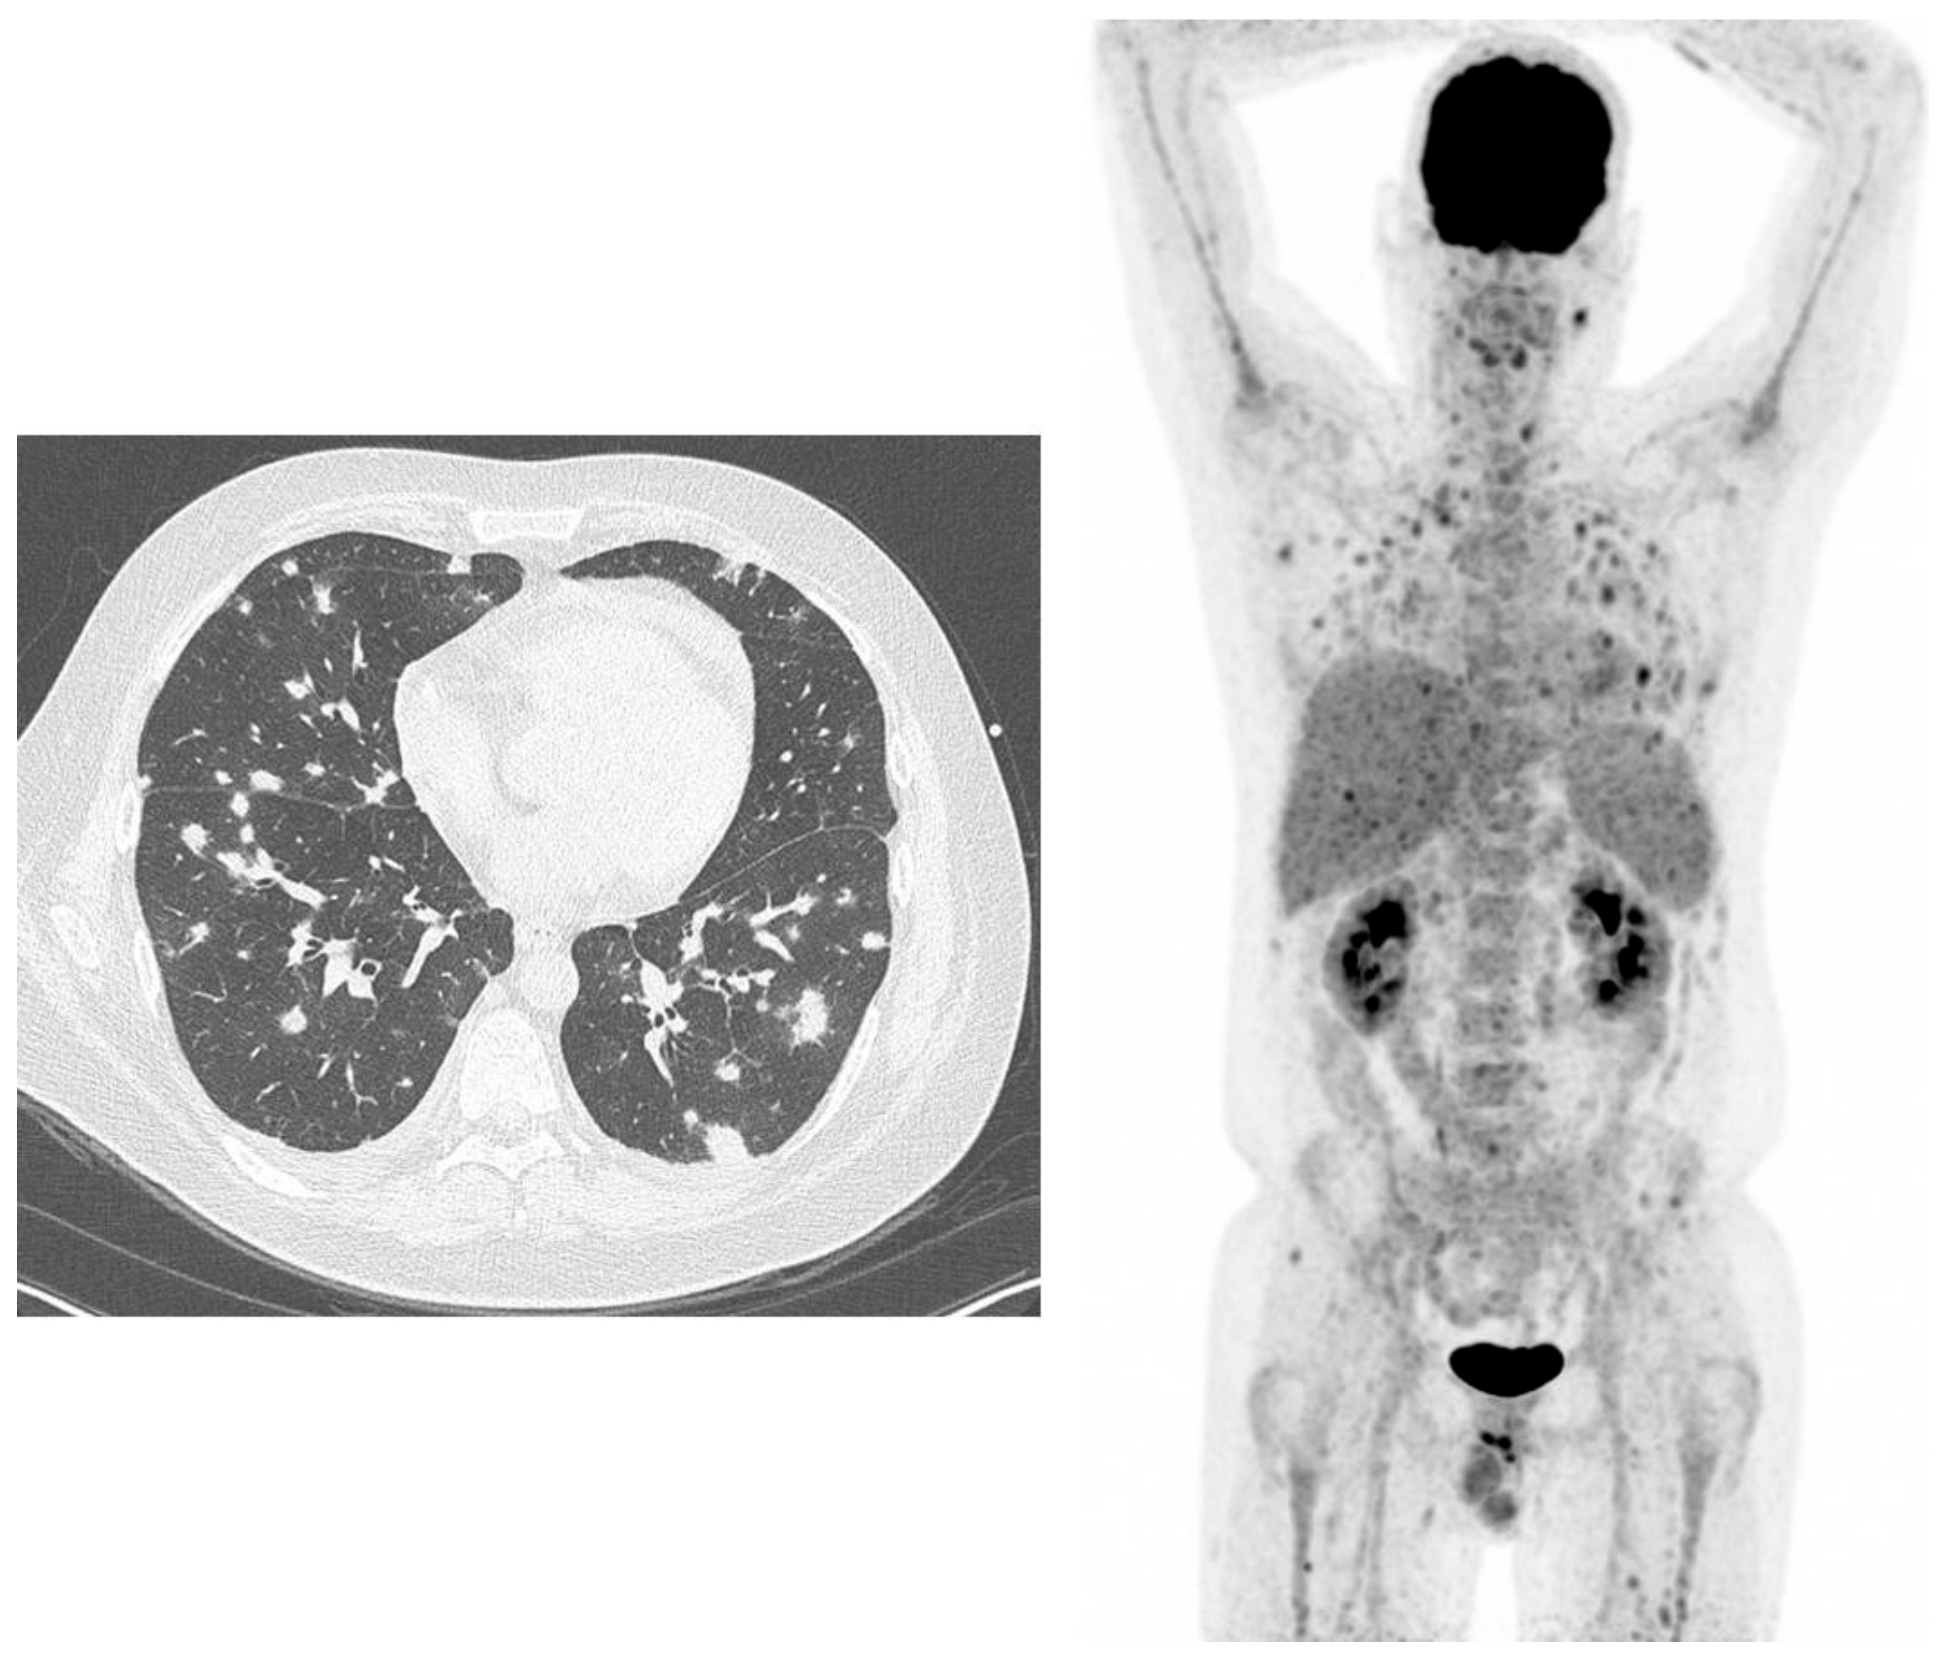

- Bertagna, F.; Bosio, G.; Caobelli, F.; Motta, F.; Biasiotto, G.; Giubbini, R. Role of 18F-fluorodeoxyglucose positron emission tomography/computed tomography for therapy evaluation of patients with large-vessel vasculitis. Jpn. J. Radiol. 2010, 28, 199–204. [Google Scholar] [CrossRef] [PubMed]

- De Boysson, H.; Aide, N.; Liozon, E.; Lambert, M.; Parienti, J.J.; Monteil, J.; Huglo, D.; Bienvenu, B.; Manrique, A.; Aouba, A. Repetitive 18F-FDG-PET/CT in patients with large-vessel giant-cell arteritis and controlled disease. Eur. J. Intern. Med. 2017, 46, 66–70. [Google Scholar] [CrossRef] [PubMed]

- Martìnez-Rodrìguez, I.; Jiménez-Alonso, M.; Quirce, R.; Jiménez-Bonilla, J.; Martìnez-Amador, N.; De Arcocha-Torres, M.; Loricera, J.; Blanco, R.; González-Gay, M.Á.; Banzo, I. 18F-FDG PET/CT in the follow-up of large-vessel vasculitis: A study of 37 consecutive patients. Semin. Arthritis Rheum. 2018, 47, 530–537. [Google Scholar] [CrossRef] [PubMed]

- Karunanithi, S.; Sharma, P.; Bal, C.; Kumar, R. (18)F-FDG PET/CT for diagnosis and treatment response evaluation in large vessel vasculitis. Eur. J. Nucl. Med. Mol. Imaging 2014, 41, 586–587. [Google Scholar] [CrossRef]

- Muto, G.; Yamashita, H.; Takahashi, Y.; Miyata, Y.; Morooka, M.; Minamimoto, R.; Kubota, K.; Kaneko, H.; Kano, T.; Mimori, A. Large vessel vasculitis in elderly patients: Early diagnosis and steroid-response evaluation with FDG-PET/CT and contrast-enhanced CT. Rheumatol. Int. 2014, 34, 1545–1554. [Google Scholar] [CrossRef]

- Henes, J.C.; Mueller, M.; Pfannenberg, C.; Kanz, L.; Koetter, I. Cyclophosphamide for large vessel vasculitis: Assessment of response by PET/CT. Clin. Exp. Rheumatol. 2011, 29, S43–S48. [Google Scholar]

- Salvarani, C.; Magnani, L.; Catanoso, M.; Pipitone, N.; Versari, A.; Dardani, L.; Pulsatelli, L.; Meliconi, R.; Boiardi, L. Tocilizumab: A novel therapy for patients with large-vessel vasculitis. Rheumatology 2012, 51, 151–156. [Google Scholar] [CrossRef]